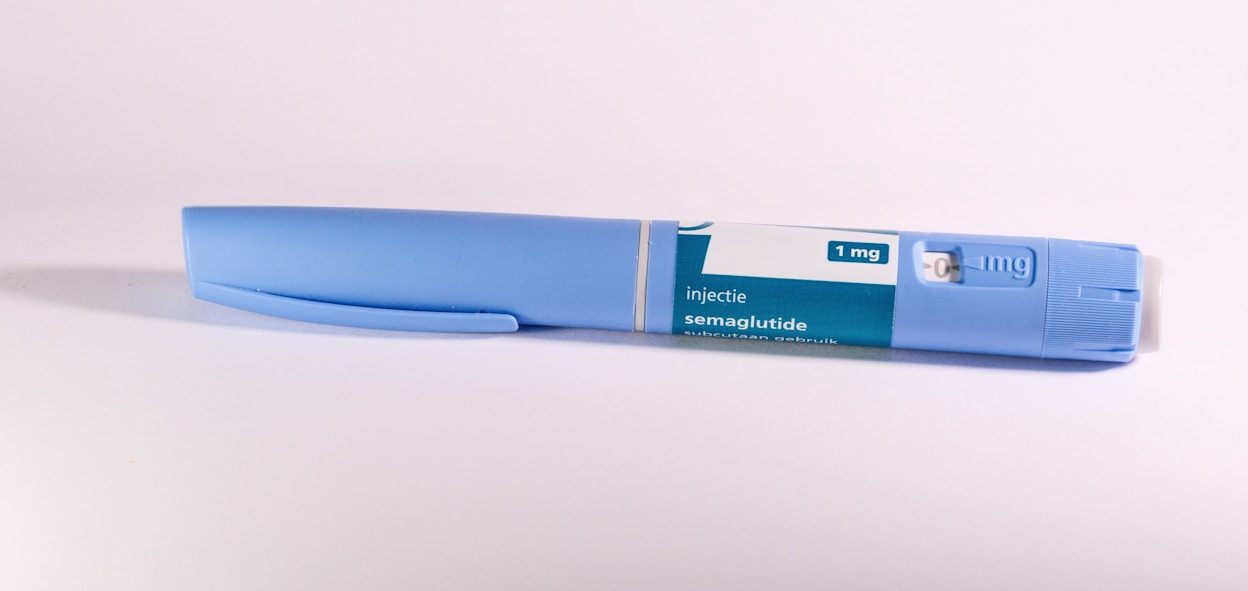

Ozempic (semaglutide) is a prescription medication primarily used for adults with type 2 diabetes to manage blood sugar levels (A1C). It is also approved to reduce the risk of major cardiovascular events (like heart attack or stroke) and slow the decline of kidney function in certain diabetic patients.

Ozempic’s active ingredient, semaglutide, belongs to a class of medicines called GLP-1 agonists. GLP-1 is a natural hormone released in the gut when we eat, helping to balance blood sugar and inducing a feeling of fullness.

This unique mechanism of action—regulating appetite and delaying gastric emptying—is why Ozempic (and its weight management counterpart, Wegovy) has shown significant effectiveness in promoting and maintaining weight loss in clinical trials. For instance, in one trial, semaglutide patients achieved 7.7 lbs (3.5 kg) more weight loss than the placebo group (with a 1 mg dose).

Important Note: Ozempic is a potent prescription drug. It is not FDA-approved for weight loss alone (Wegovy is). Patients must consult a healthcare provider to fully understand the risks, contraindications (such as a personal or family history of medullary thyroid carcinoma), and ensure proper injection technique.